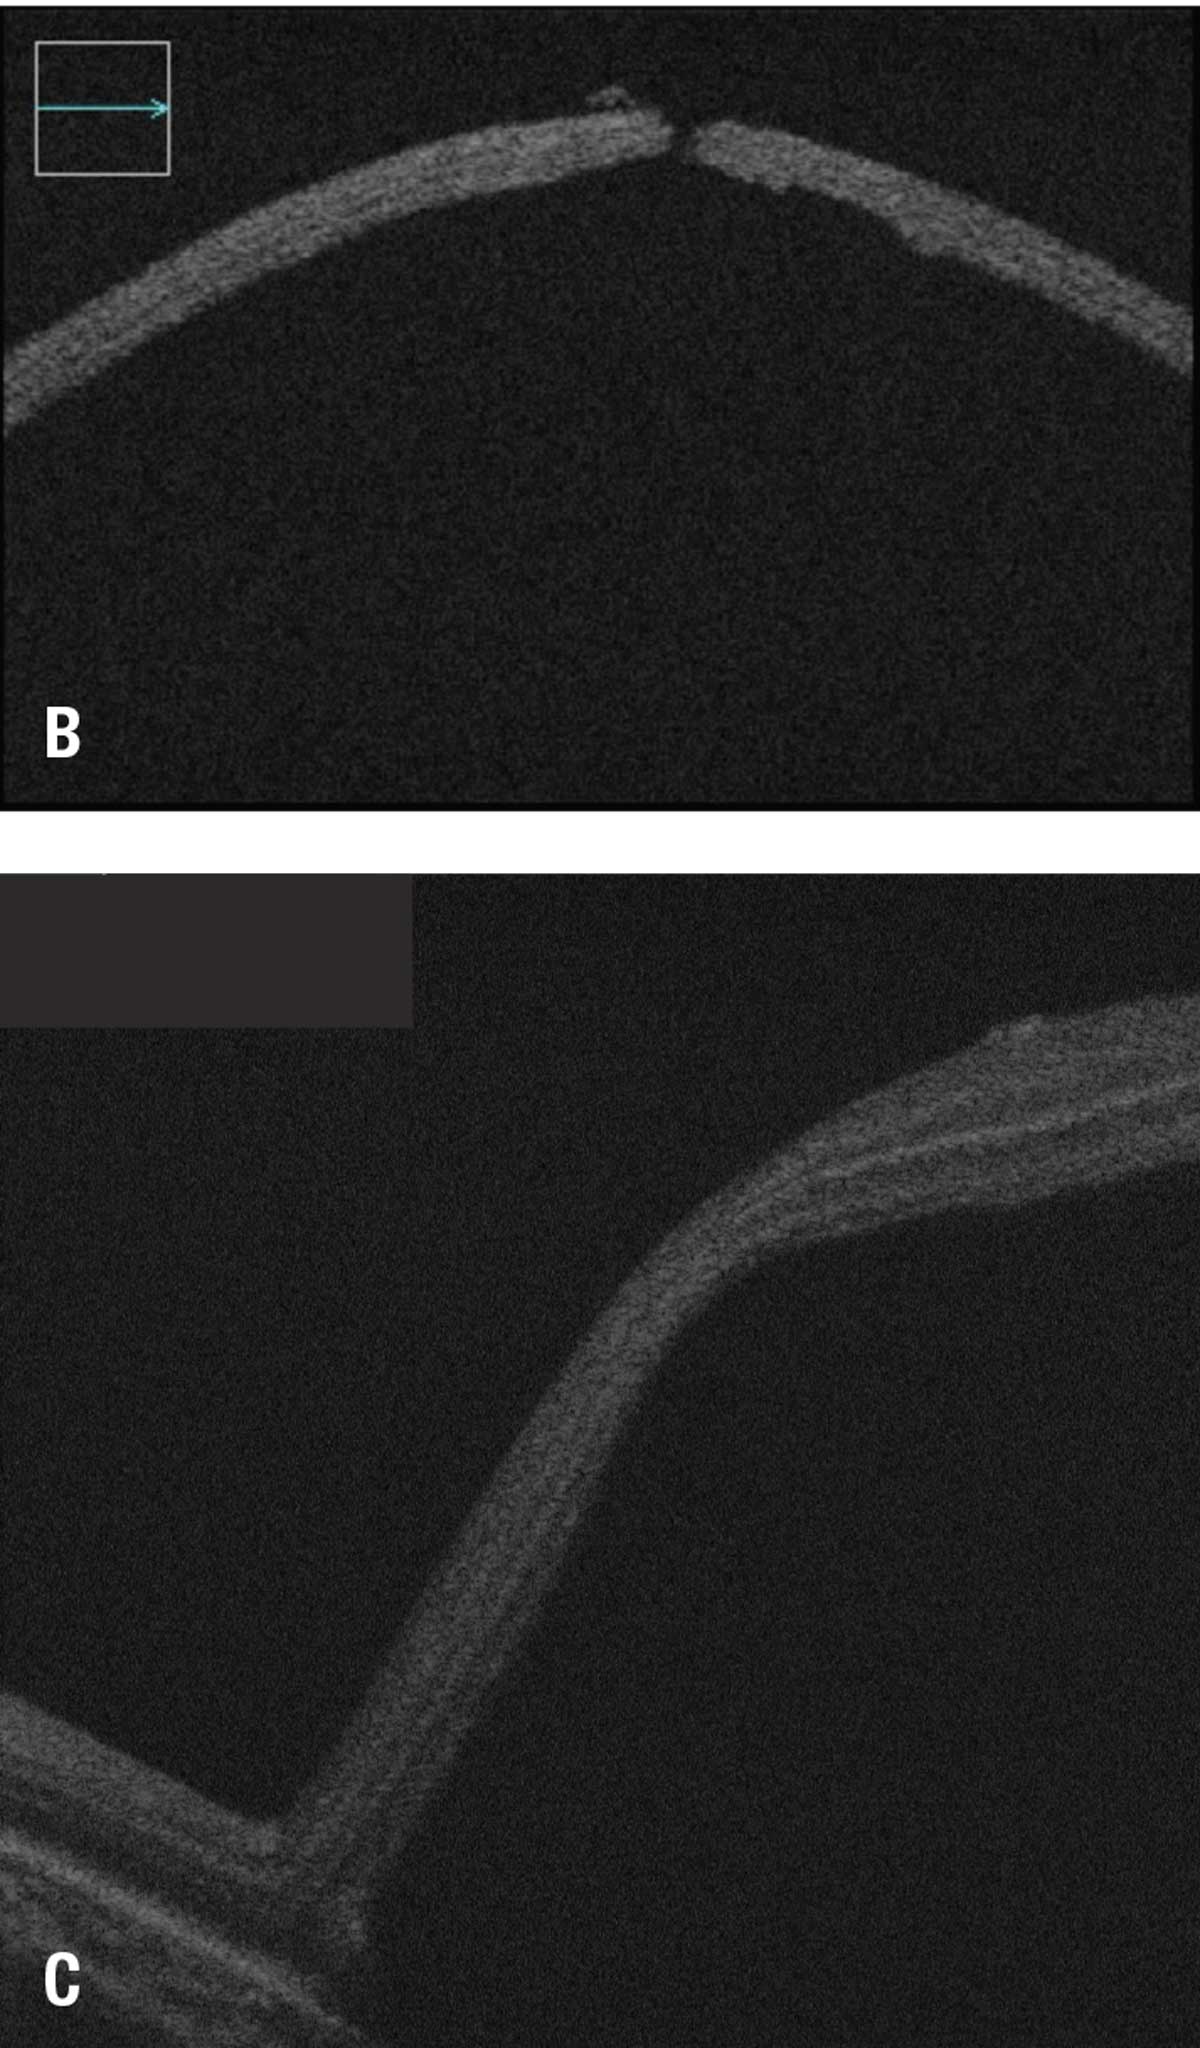

Another important adjunct is the use of intraoperative ocular coherence tomography guidance to precisely determine the location and extent of the bleb, including the ability to monitor for fovea detachment during delivery (Figure 2).

| Figure 2A. Subretinal delivery of voretigene neparvovec-rzyl into the right eye of a 22-month-old girl. Bleb creation using intraoperative optical coherence tomography guidance. |

| Figures 2B and 2C. B) OCT cross-sectional view of the retinotomy site in same patient as figure 2A. C) Intraoperative monitoring of foveal detachment in same patient. |